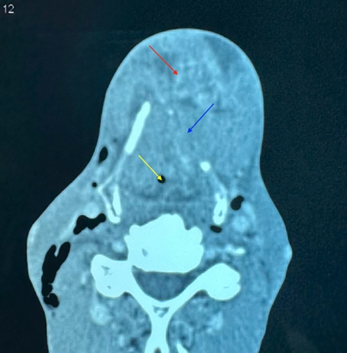

Figure 2: Axial CT scan at the

level of the thyroid cartilage showing a laryngeal mass narrowing the airway

lumen (yellow arrow), with thyroid cartilage lysis (blue arrow) and invasion of

the anterior cervical soft tissues (red arrow)